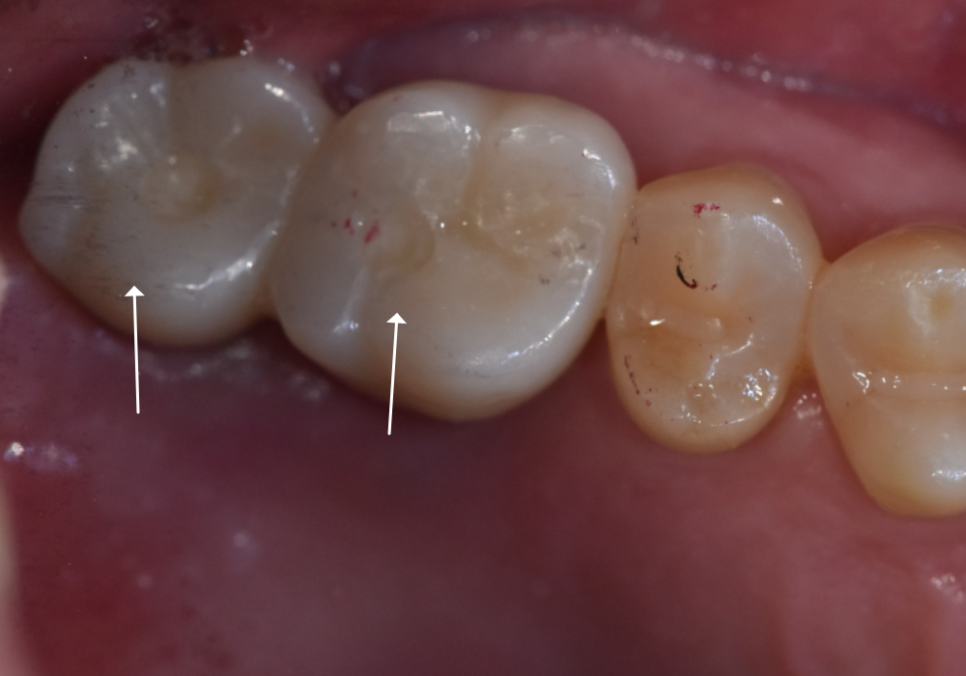

240313 (전) 241102 (후)

가장 안전하고 튼튼한 길을 가기 위해

충분한 시간을 두고 기다렸고,

4개월 뒤 드디어 임플란트를 완성해 드렸습니다!

241102